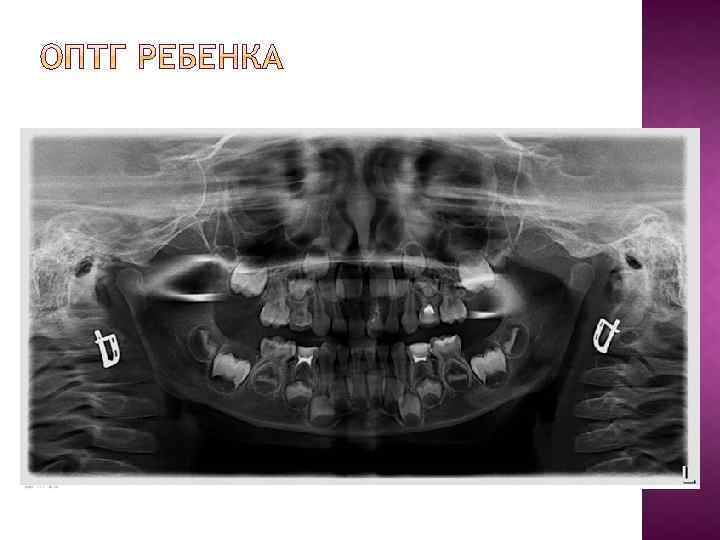

Введение Что такое ортопантомограмма (ОПТГ) и для чего она нужна? Когда нужна ОПТГ? Схема ортопантомограммы Методика чтения ОПТГ Методика съемки Основные ошибки при съемке ОПТГ взрослого человека ОПТГ ребенка Коллекция снимков Заключение

Большинство стоматологических материалов изготавливаются рентгеноконтрастными. Делается это для того, чтобы можно было контролировать объем и расположение этого материала на рентгеновских снимках. Например, пломбировочные материалы для корневых каналов на снимке обозначены буквой А. Ортопантомография дает хорошее представление о расположении зубов мудрости (на снимке буква С). Даже прицельные снимки не дают полной картины о строении и локализации восьмерок. Поэтому без проведения ОПТГ я крайне не рекомендую браться за удаление или лечение "мудрых" зубов.